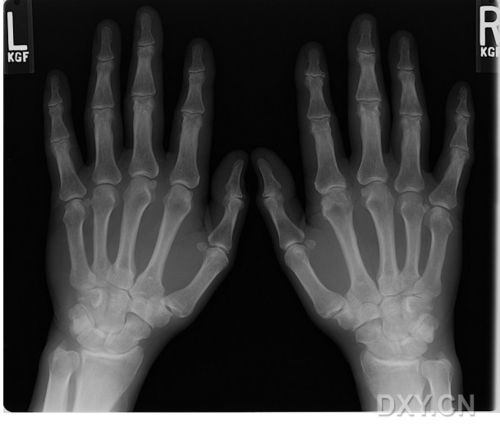

x光照片手

x光照片手,x光照片

要一张左右手手掌骨骼图,x光的要,ct的图

x光手骨正常照片

手部x光图片

正常右手x光片图片

正常人手x光图片

x光手骨

手掌x光

正常右手x光片